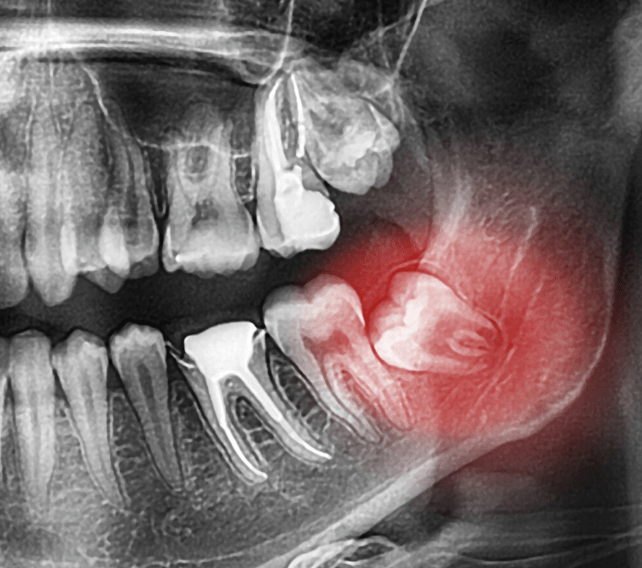

Periapical abscess | Radiology Case | Radiopaedia.org

Treatment of a dental abscess | Ralev Dental Clinic

Dental abscess: What Are The Possible Treatments? – Emergency Dentist

Dental Abscess or Infection | Dentist West Haven, Milford, CT

Tooth abscess symptoms: What is a dental abscess, how do you fix it …

Tooth Abscess – What to do? Signs, Symptoms & Treatment – Malvern …